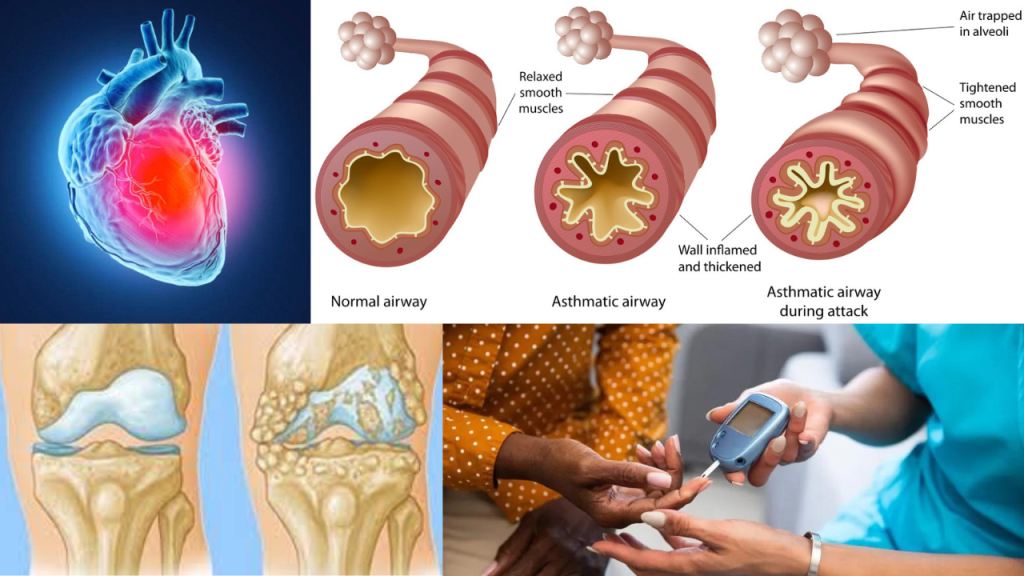

1.हृदय रोग

हृदय रोग बीपी व कोलेस्ट्रॉल बढ़ता है या मौसम |

कम तापमान से रक्त वाहिकाएं सिकुड़ती हैं जिससे रक्त का इन वाहिकाओं से गुजरने के लिए अधिक बल लगाना पड़ता है | इससे ब्लड प्रेशर बढ़ जाता है| वहीं सर्दियों में नहीं तले हुए और गरिस्ट भोजन की मात्रा बढ़ती है| जिससे बेड कोलेस्ट्रोल का स्तर बढ़ सकता है इससे हार्ट अटैक और कार्डियक अरेस्ट का खतरा बढ़ जाता है |

उपाय – रोज 20 मिनिट वॉक व प्राणायाम करें

रोज 20 से 30 मिनिट वॉक करें यार रक्त संचार को बढ़ती और रक्त वाहिकाओं में आई शक्ति घटती है इससे हार्ट अटैक का खतरा घटना और प्राणायाम ध्यान से भी फायदा होता है |

2.अस्थमा

अस्थमा वायु मार्ग प्रभावित करता है |

तेज ठंडी गांड छाती में वायु मार्ग शक्ति हो जाता है जिससे सांस लेना मुश्किल हो जाता है अस्थमा पीठ दर्द भी हवा के लिए मुंह से सांस लेना शुरू कर देते हैं परिणाम स्वरुप स्वस्थ हवा सांस के माध्यम से फेफड़े प्रवेश करने लगती है जिससे वायु मार्ग में इन्फ्लेमेशन होने लगता है

3.डायबिटीज

स्ट्रेस से शुगर बढ़ता है डायबिटीज |

4.अर्थराइटिस

अर्थराइटिसब्लड फ्लो धीमा होता है |

ठंडा मौसम कटिया के दर्द को बढ़ा सकता है तेज ठंड से ब्लड फ्लो धीमा हो सकता है दर्द के प्रति शेयर की संवेदन बढ़ जाती है अक्सर जैसे-जैसे तापमान गिरता है वायुमंडल में हवा के दबाव बैरोमीटर का दबाव की मात्रा भी बदल जाती है इसमें से कुछ लोगों को जोड़ों में दर्द बढ़ता है |